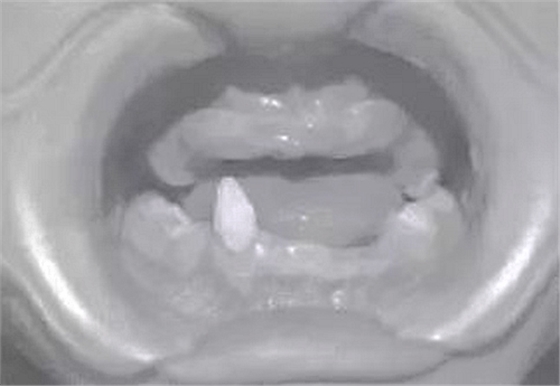

患兒,男,8歲,因“先天缺牙2年.要求鑲牙”于2010年7月就診于我科?;純杭议L訴孩子牙齒先天發(fā)育不良,無法咀嚼,擔心孩子發(fā)育。檢查示:患兒智力正常,頭發(fā)及眉毛稀少,雙側(cè)面部對稱,囟門發(fā)育不足,腳趾并攏不全,口內(nèi)查11、12、13、14、15、21、22、23、24、25、31、32、33、34、35、41、42、44、45缺失,75、85為乳牙,43為錐形牙。牙槽嵴較低平,上下牙槽嵴未觸及明顯的骨突及骨尖,無咬合關(guān)系,頜間距短。雙側(cè)顳下頜關(guān)節(jié)區(qū)無壓痛、無關(guān)節(jié)彈響。

圖2患者修復(fù)前口內(nèi)像